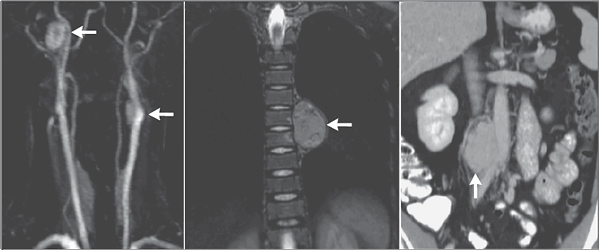

Реноваскулярная гипертензия (5%)

Диагностика

• Резистентная гипертензия, сердечная недостаточность.

• Абдоминальный систоло-диастолический шум, шум над сонными, бедренными артериями.

• Прогрессирующее снижение функции почек (спонтанно или в ответ на ИАПФ).

• Разница длины почек >1.5 см.

• Дуплексная допплерография почечных артерий.

• Магнитно-резонансная 3-мерная ангиография с гадолинием.

• Компьютерная томографическая ангиография.

• Двусторонняя селективная почечная артериография.

Лечение

• ИАПФ или БРА (без двустороннего стеноза).

• Ангиопластика/стенты (при атеросклерозе в случае прогрессирования дисфункции почек, неконтролируемой гипертензии).

• Хирургия сосудов.

АКТГ-продуцирующий мелкоклеточный рак парааортально у пациенки 75 лет с гипертензией, ожирением и гипокалиемией.